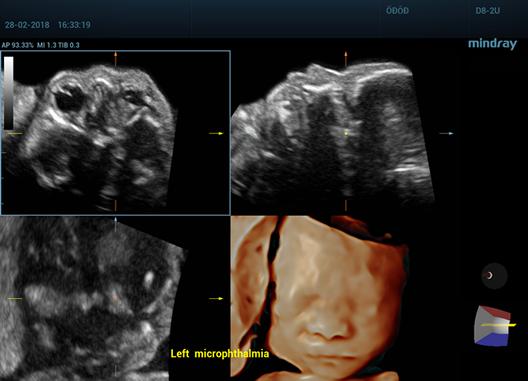

Care este diferenta dintre ecografia 2D, 3D si 4D?

Foto 1/7